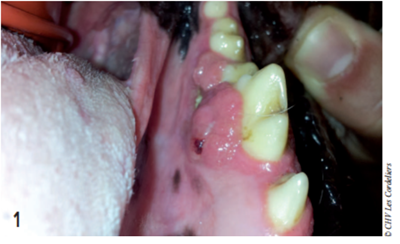

Le cas nous a alors été référé. Lors de sa consultation, trois semaines après la première excision, l’examen de la bouche sous anesthésie générale révélait à nouveau la présence d’un tissu bourgeonnant sur la face linguale de la gencive en regard de la carnassière (photo 1).

Photo 1 : Photographie de la tumeur, trois semaines après la première exérèse.